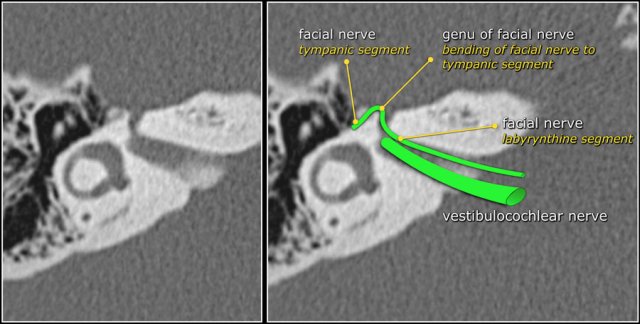

Facial nerve

The labyrinthine segment of the facial nerve coming from the internal auditory canal angles sharply forward, nearly at right angles to the long axis of the petrous bone, to reach the geniculate ganglion.

At the ganglion the facial nerve makes a U-turn (first genu of the facial nerve) to run posteriorly as the tympanic segment along the medial wall of the epitympanum.